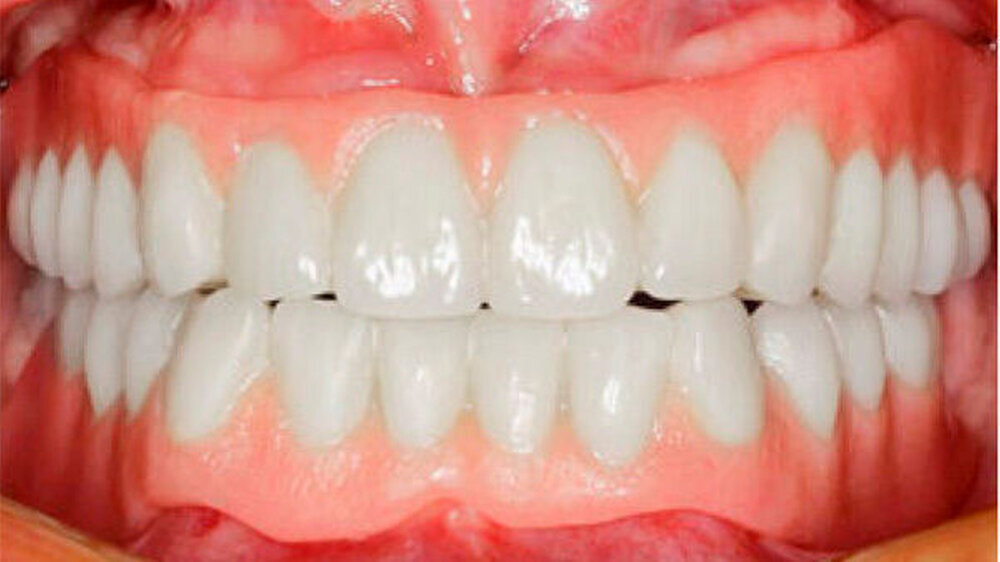

Der bei Behandlungsbeginn 14-jährige Patient war mit einer neun beziehungsweise fünfjährigen Prothese im Unter- beziehungsweise Oberkiefer versorgt (Abb. 2 und 3). Die angelegten Zapfenzähne 12, 11 und 21 waren bereits mehrfach konservierend restauriert und wiesen diverse Stellen mit Sekundärkaries auf. Die Kronenränder der Zähne 33 und 43 waren deutlich sondierbar. Der Kieferkamm im Unterkiefer war aufgrund der fehlenden Zahnanlagen sehr schmal (Abb. 4 bis 6). Die Panoramaschichtaufnahme zeigte das reduzierte vertikale Knochenangebot (Abb. 7). Da die Vitalerhaltung der wenigen Restzähne aufgrund des jungen Alters des Patienten unbedingt anzustreben war, wurde als Behandlungsziel im Ober- und Unterkiefer eine Versorgung mit Hybridprothesen, retiniert auf Teleskopkronen, festgelegt.

Durch Einbeziehung der Restbezahnung als Pfeilerzähne, und unter Beachtung deren Vitalerhaltung konnte der Patient funktionell und ästhetisch mit stabil verankerten Hybridprothesen rehabilitiert werden (Abb. 14 und 15). Teleskopkronen und -prothesen weisen Studien zufolge eine gute Langzeitprognose auf. Eine regelmäßige Nachsorge ist aber entscheidend für den Erfolg der Rekonstruktion. Da die Speichelmenge bei diesem Patienten im Normbereich liegt, ist diesbezüglich nicht von einem erhöhten Kariesrisiko auszugehen. Eine ungenügende Mundhygiene oder Mitarbeit hingegen stellen Risikofaktoren für biologische Komplikationen wie Parodontitis oder Karies dar. Nachteilig für den Erfolg der Rekonstruktion kann sich die relativ geringe Pfeilerzahl und deren Verteilung im Kiefer auswirken (Wöstmann et al. 2007).